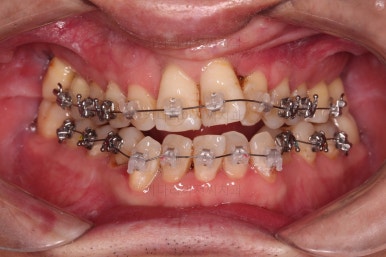

5. 치료과정 및 경과

본격적인 부산구순구개열교정 치료 전에 필요한 부위의 충치치료를 진행합니다.

위아래 장치를 부착했습니다.

초기 단계의 주안점은 아랫니와 악궁과 어울리는 윗니 악궁의 형태를 만들어 주는 것이고요.

악궁확장장치를 사용하지 않은만큼 철사의 형태를 잘 잡아가면서 악궁 형태를 개선시킵니다.

교정 10개월째인데, 악궁형태 많이 좋아졌고, 가지런한 느낌도 많이 좋아졌습니다.